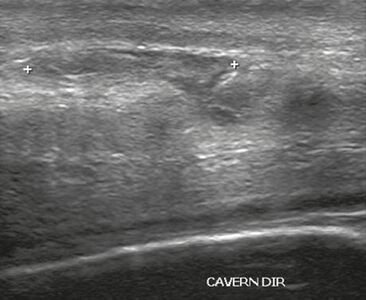

The corpora cavernosa are homogeneous and relatively hypoechoic cylindrical structures lined with tunica albuginea, a thin membrane that has a thickness of approximately 2 mm when the penis is flaccid and 0.25 mm when it is erect. The corpus spongiosum, a ventral, medial body that is more echoic than the corpora cavernosa, is also covered by the tunica albuginea and contains the urethra. As can be seen in Figures 1 and 2, it is more dilated and prominent in its proximal segment, known as the bulb, and in its distal segment, constituting the glans. Buck's fascia is superficial to the tunica albuginea and covers all of the structures described.[1]

Venous drainage is performed by the deep and superficial dorsal veins of the penis. The dorsal arteries of the penis are located adjacent to the deep dorsal vein and a cavernous artery is located in the center of each corpus cavernosum. On color Doppler, the cavernous arteries present single phase flow. In the flaccid penis (Figure 3), the normal cavernous arteries show a systolic peak between 11 and 20 cm/s. At the beginning of erection, the systolic and diastolic flows undergo progressive increases. When vein occlusion begins, the diastolic flow decreases progressively, and once stiffness is established, it becomes negative.[1]